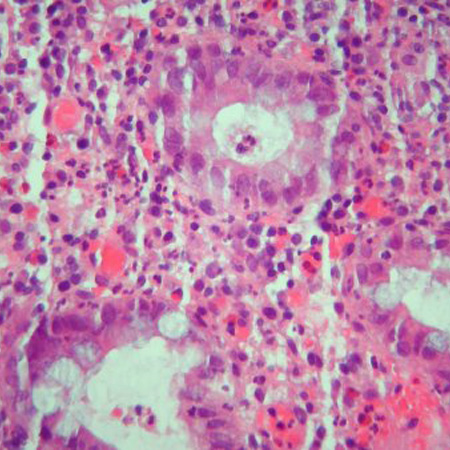

Colonoscopy and biopsy may be helpful when investigating Crohn's disease, microsporidia, cytomegalovirus (CMV) infection, and histoplasmosis, while colonoscopy/endoscopy and biopsy may be helpful when investigating lymphoma. Capsule biopsy is emerging as a promising test for diagnosing early lesions of Crohn's disease.[Figure caption and citation for the preceding image starts]: Significant inflammation in the colonic wall, widening of submucosa, and dense lymphoid aggregates in the submucosaCourtesy of Drs Wissam Bleibel, Bishal Mainali, Chandrashekhar Thukral, and Mark A. Peppercorn; used with permission [Citation ends].

[Figure caption and citation for the preceding image starts]: Cryptitis and crypt abscess with morphological distortion of the crypts accompanied by inflammation and abundant lymphatic and plasma cellsCourtesy of Drs Wissam Bleibel, Bishal Mainali, Chandrashekhar Thukral, and Mark A. Peppercorn; used with permission [Citation ends].